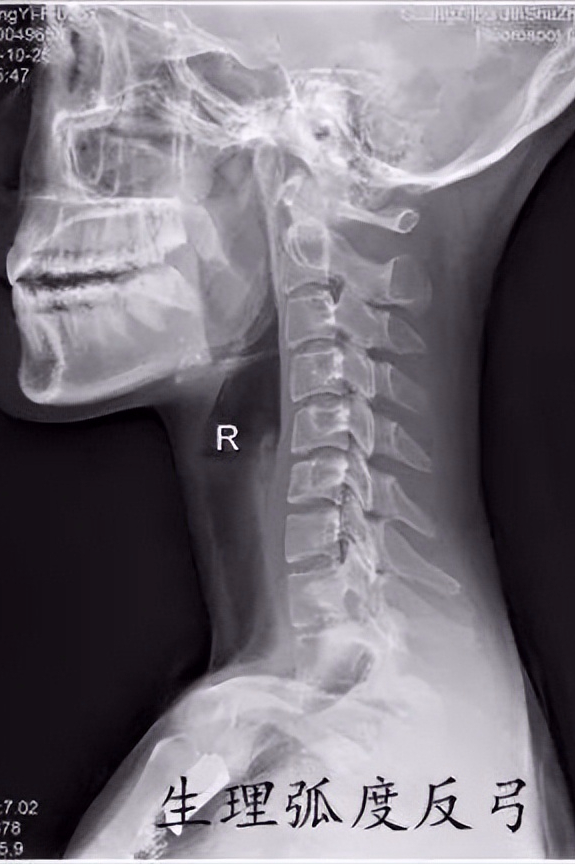

现在的年轻人大多长时间低头看电脑或则低头看手机,经常出现颈部疼痛、落枕、头晕头痛等不适,就诊拍片子经常能看到如下这些情况

这些片子提示你的颈椎的生理弯曲已经消失,甚至出现了反弓。为啥会出现这种情况呢?

其次为啥它会消失呢?主要是因为长时间的姿势不良导致的。低头时颈椎的生理弯曲会消失,长时间低头会导致肌肉过度紧张,导致身体前后肌肉力量不平衡,进而出现颈椎的生理弯曲消失。生理弯曲消失后,颈椎受力情况改变,小关节承受的压力增大,加剧退化;颈椎椎间盘受力增大,退化提前,可能导致椎间盘突出等情况发生。